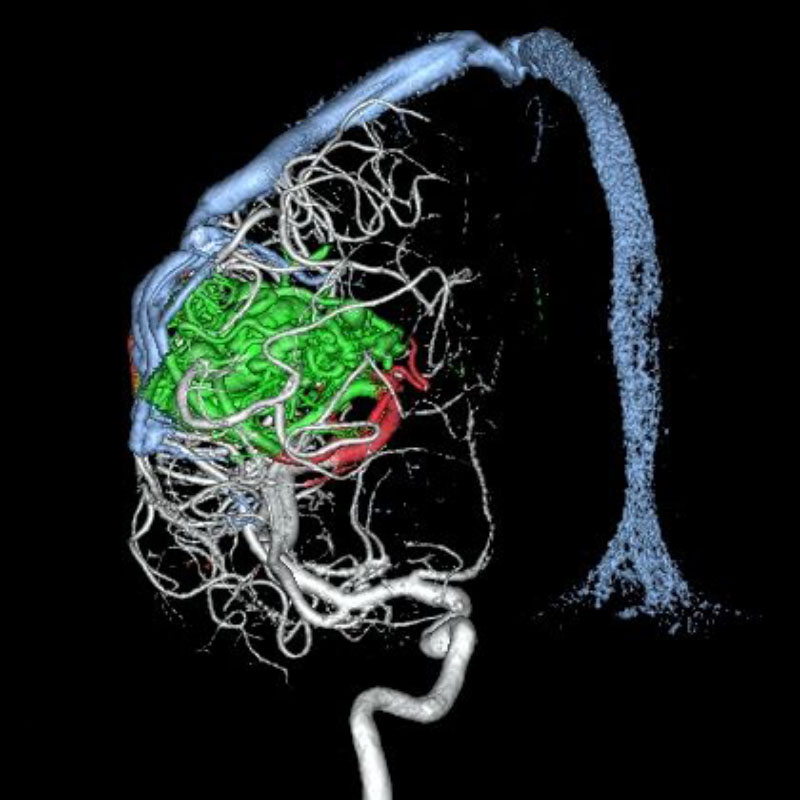

脳動静脈奇形

血管塞栓術

松田/濵田/元永